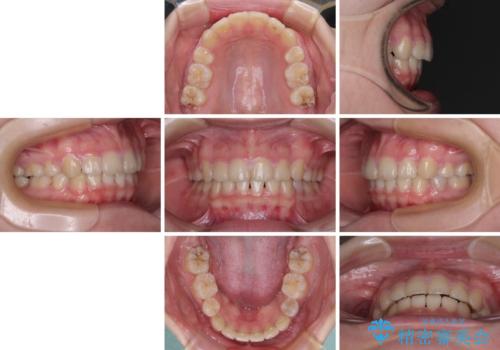

舌の突出癖があり、咬合力も強かったため、治療期間は長くなることが懸念されましたが、舌のトレーニングをしっかりと行っていただいたこともあり、2年弱で治療を終えることができました。

上下ともに歯列が前方に突出していたため、上下左右の第一小臼歯4本を抜去する方針(既に上顎は抜歯されています)で、ワイヤー装置による矯正治療を行うこととしました。

舌の突出癖による影響もあったため、舌のトレーニングを並行して実施しました。